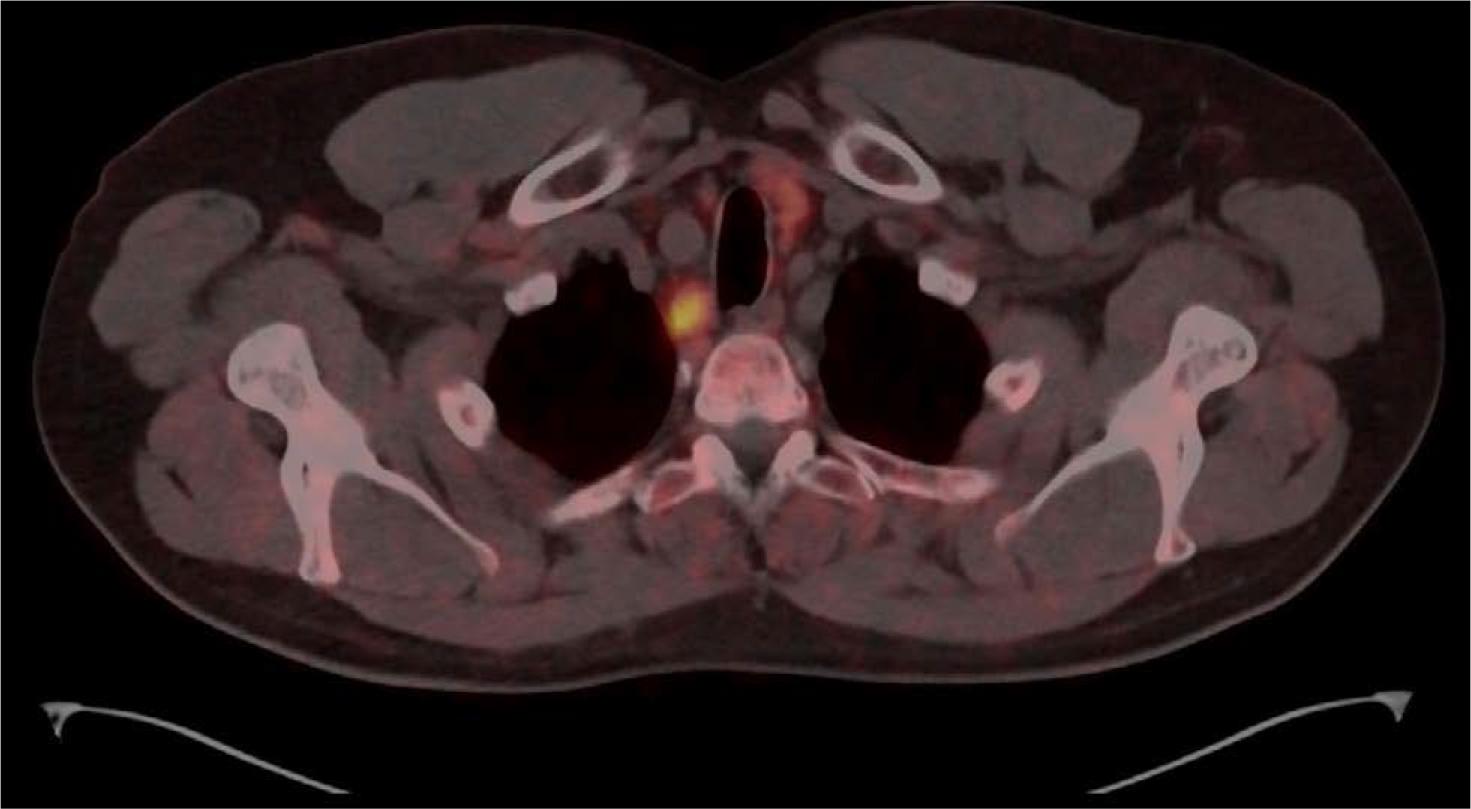

[68Ga]Ga-DOTA-TATE PET/CT, axial plane-increased focal uptake below the lower pole of the right thyroid lobe, which corresponds with a hyperactive parathyroid or parathyroid adenoma. Additionally, mild uptake was observed within two foci in the lower pole of the left thyroid lobe, which required further differentiation between an additional hyperactive parathyroid and a focal lesion in the thyroid.

Shortly after, [68Ga]Ga-DOTA-TATE PET/CT was performed. The scan ultimately confirmed increased somatostatin receptor expression in the previously visualized pancreaticoduodenal lesions, specifically in the pancreas, near the head of the pancreas, and tangentially to the wall in the duodenum, which was consistent with a previously suspected neuroendocrine tumor. In soft tissues, increased expression of somatostatin receptors was visualized in the form of a hyperactive parathyroid located inferiorly and dorsally from the lower pole of the right thyroid lobe and within two foci in the area of the lower pole of the left thyroid lobe, which required further assessment to differentiate between a hyperactive parathyroid and focal lesion in the thyroid.